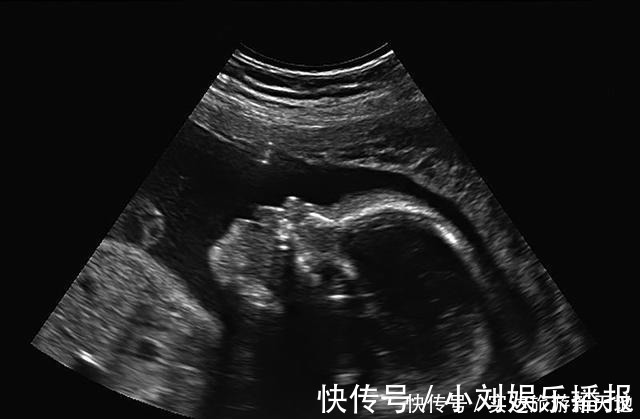

B超单|孕期B超单直接反应胎儿状况,这5处孕妈要学会看懂,医生不会详说

经过紧张的备孕,宝宝终于来到了我们的身边。为了宝宝能够健康成长,我们都会去产检。可B超单上却让我们无比郁闷,到底宝宝怎么样呢?孕早期B超单上的这两个数据,暗示了胎儿“小秘密”,孕妈千万别忽略。

1、宝宝头臀长孕早期宝宝一般大约有5厘米长,在子宫内都是身体蜷缩的姿态,想要测量宝宝的长度是比较难的。所以大家一般会选择测量宝宝的头臀长。头臀长是指宝宝头部最顶端到宝宝臀部最底端的距离。正常的头臀长标准数据如下:孕期2个月:(3.27cm至4.14cm)孕期3个月:(4.3cm至5.29cm)孕期4个月:(5.47cm至6.59cm)孕期5个月:(6.78cm至8.02cm)具体测量孕周方法的公式:孕周期=CRL+6.5,假如,B超数据单的头臂径是6.03厘米,那么宝宝的孕周期是6.03+6.5=12.53周。

2、宝宝的NT检查数值NT检查是指宝宝颈部的空隙位置的颈项透明层厚度。正常情况下,这里应该是透明的,因为这是宝宝新陈代谢所产生的积液,是对宝宝的一种保护。NT检查目的是在孕妇怀孕初期来诊断宝宝是否有染色体疾病,比如21三体综合征等胎儿异常,是早期排除宝宝是否发育正常的检查。

NT检查一般在孕妇怀孕3个月左右去做的检查。宝宝NT的正常厚度是要小于3mm的。如果NT检查的结果显示厚度大于3mm,这就警示我们要注意:胎儿发育可能不是那么健康。在检查报告中,一般也会显示胎儿的染色体是否存在异常现象,胎儿发育是否健康,没有畸形。孕妇后面还会做唐氏筛查来排查宝宝是否发育良好,医生也会重点关注,必要时孕妇可以多做些检查综合判断,例如无创DNA检查、羊水穿刺检查、胎儿染色体检查等。